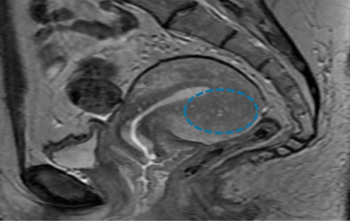

New research compared the effectiveness of MRI and TVS for detecting rectosigmoid endometriosis.